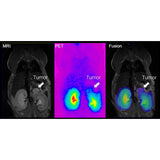

Combining PET with MRI enhances the capabilities to study detailed morphological changes in different organs and tumours, adding more precise information of the distribution and behaviour of the PET tracer.

Bruker’s sequential PET/MR instruments are offered at 3T for translational research and at 7T and 9.4T for high-field applications in mice and rats using Bruker’s BioSpec Maxwell MRI technology. This is combined with Bruker’s SiPM PET technology, providing the highest sensitivity, high spatial resolution and precise quantification across the entire FOV. A touch screen controlled motorized animal transport system simplifies the workflow and supports a broad spectrum of application fields, such as oncology, functional and anatomical neuroimaging, cardiac imaging and stroke models. All of this powered by the Paravision 360 software, allowing MRI users to follow familiar MR imaging workflows to obtain valuable PET/MR data immediately.

- Streamlined workflows including automatic image stitching, MR based attenuation correction and PET/MR image fusion